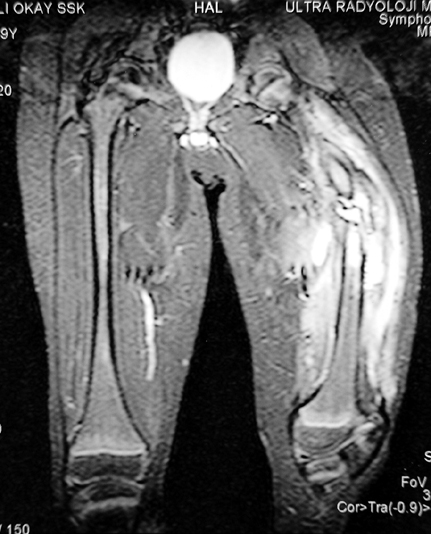

Kronik osteomiyelit, kemik ve yumuşak dokularda nekroza yol açar. Ölü kemik, patojen mikroorganizmalara ev sahipliği yapan bir nidus oluşturur. Konağın savunma sistemleri, mikroorganizmalarla baş etmek için sıklıkla optimal koşullarda değildir. Dolaşım bozukluğu yüzünden enfeksiyon bölgesine antibiyotikler yeterince ulaşamaz. Bu nedenle ölü dokuların ortamdan tamamen uzaklaştırılması gerekir (radikal debridman).

Uygun radikal debridman tüm nekrotik kemik ve yumuşak dokuların çıkartılmasını gerektirir, ve sıklıkla uzuvda instabiliteye neden olur. Kalan kemik ve yumuşak doku defektinin bir şekilde fiksasyonu ve rekonstrüksiyonu gereklidir. İlizarov’un ortaya koyduğu distraksiyon osteogenezi yöntemi, kaynamanın elde edilmesi, deformitenin düzeltilmesi, bacak boy eşitsizliğinin giderilmesi ve segmental defektlerin rekonstrükte edilmesi için başarıyla kullanılmaktadır.